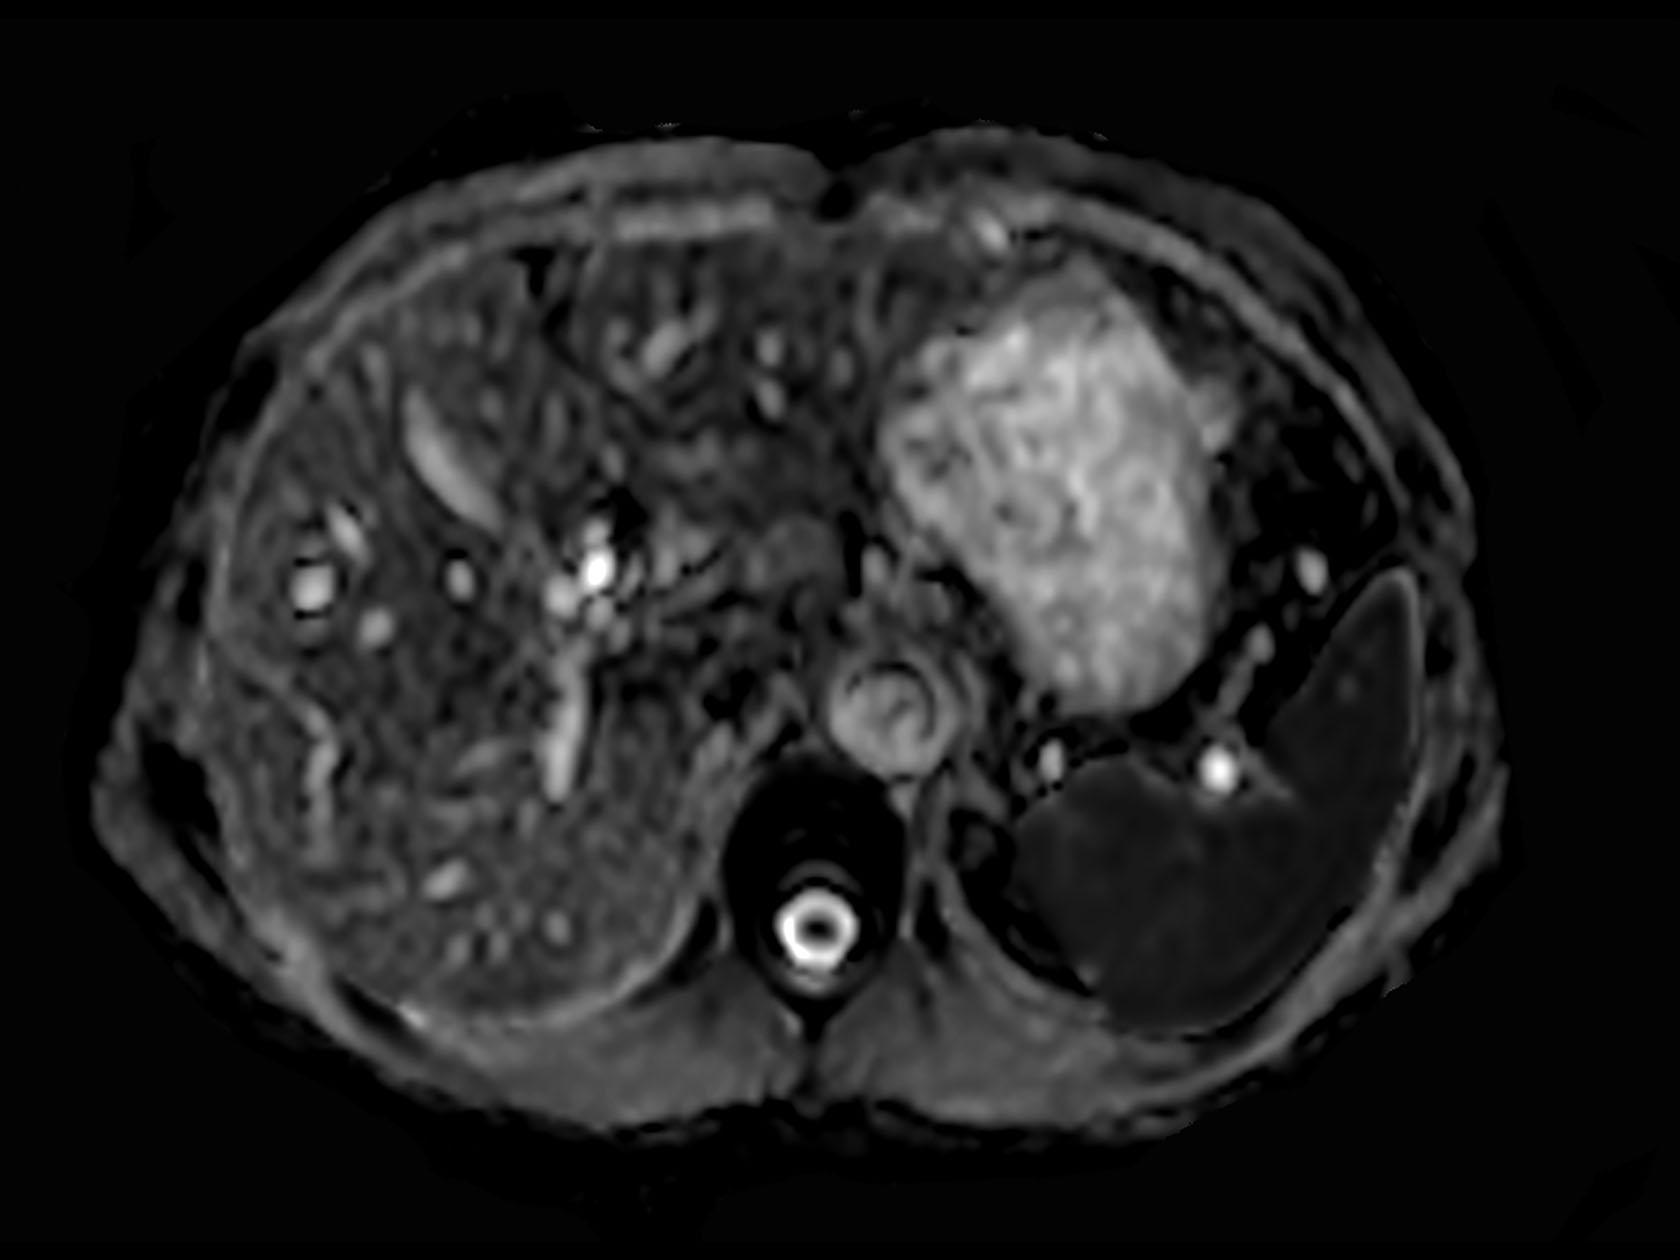

Diffusion (b1000)